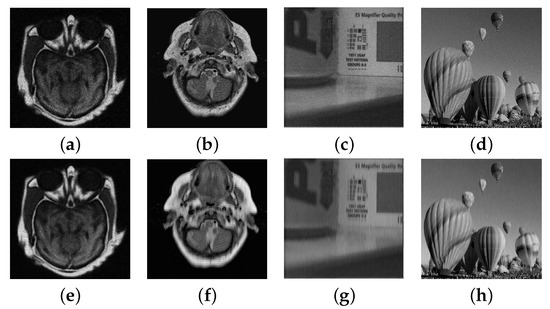

4.3. Numerical Experimental Results and Analysis

| Test Images | Peak | Noisy | PSNR | |||

|---|---|---|---|---|---|---|

| IR1/VIS1 | 155 | 26.71/26.70 | 27.72/28.89 | 2.18 | 0.23 | 0.40 |

| 255 | 28.90/29.21 | 29.29/30.47 | 2.62 | 0.24 | 0.41 | |

| IR2/VIS2 | 155 | 25.01/25.80 | 27.63/28.30 | 1.67 | 0.29 | 0.24 |

| 255 | 27.18/28.00 | 28.61/29.57 | 2.12 | 0.31 | 0.23 |